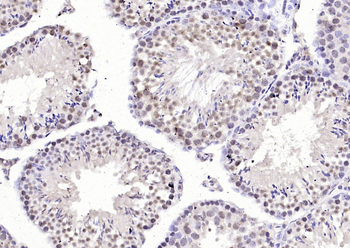

应用稀释比例:WB=1:500-2000, IHC-P=1:100-500, IHC-F=1:100-500, IF=1:100-500

文献和实验:使用 Anti-phospho-Akt (Ser473) Rabbit mAb 对石蜡包埋的人乳腺癌组织进行免疫组织化学分析。(图 A)使用免疫组化试剂盒M&R HRP/DAB Detection IHC Kit,抗体 1:100 稀释;(图 B) 采用普通免疫组化试剂盒,抗体 1:25 稀释。 图 6 免疫组化实验检测 Erk1/2 表达 注:使用 Anti-Erk1/2 Mouse mAb与p44/42 MAPK (Erk1/2)Rabbit mAb 对正常小鼠心脏组织进行免疫